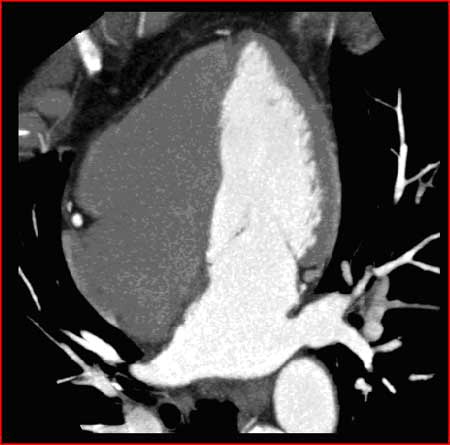

Dye is filling the left ventricle during cardiac CTA